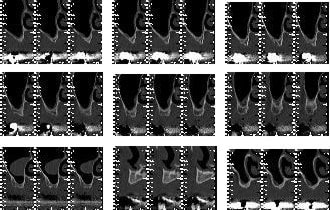

La technique d'élévation sinusienne grace à des ballonnets par voie crestale, technique appelée MIAMBE (Minimally Invasive Antral Membrane Balloon Elevation) est une technique fiable mais destinée à des élevations ponctuelles pour des unitaires. Cette technique n'est pas vraiment indiquée pour la réalisation d'une élévation sinusienne intéressant plusieurs dents (à moins d'avoir un plancher sinusien très plat).

Cela n'est techniquement pas impossible à condition de pratiquer plusieurs puits d'entrée.

Donc pxav, je ne suis pas sûr que le problème vienne du ballonnet mais plutôt de l'indication que tu as fait de cette technique.